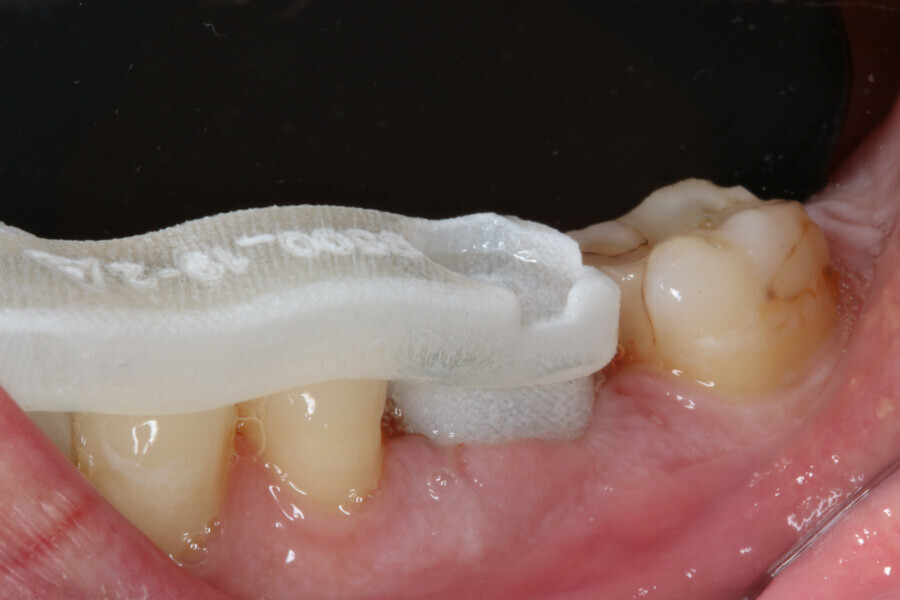

Immediately after implant placement (Fig. 5), the abutment position was registered with an intra-oral scan using Primescan (Dentsply Sirona; Fig. 6). At the end of the surgical procedure, the socket was grafted with Symbios (Dentsply Sirona) and a healing abutment was seated (Fig. 7). Radiographic evaluation was performed on the same day (Fig. 8). On basis of an intra-oral scan, an Atlantis abutment and Atlantis provisional crown were designed and fabricated with an Atlantis IO FLO (Fig. 9).

One week after implant surgery, healing was satisfactory and the abutment and provisional crown were inserted (Figs. 10–14).